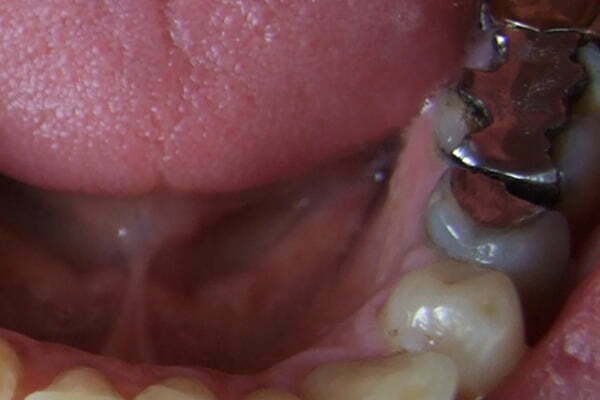

In the laboratory, we see upward of three patients a day, many of whom want to replace their old porcelain bonded crowns with new ceramic units. The main reason for this is the typical gum recession and black line associated with porcelain bonded crowns.

Even after many years we do not see gum recession and certainly no black lines when all ceramics are used. Please see the photos to the left showing how successful metal free can be.